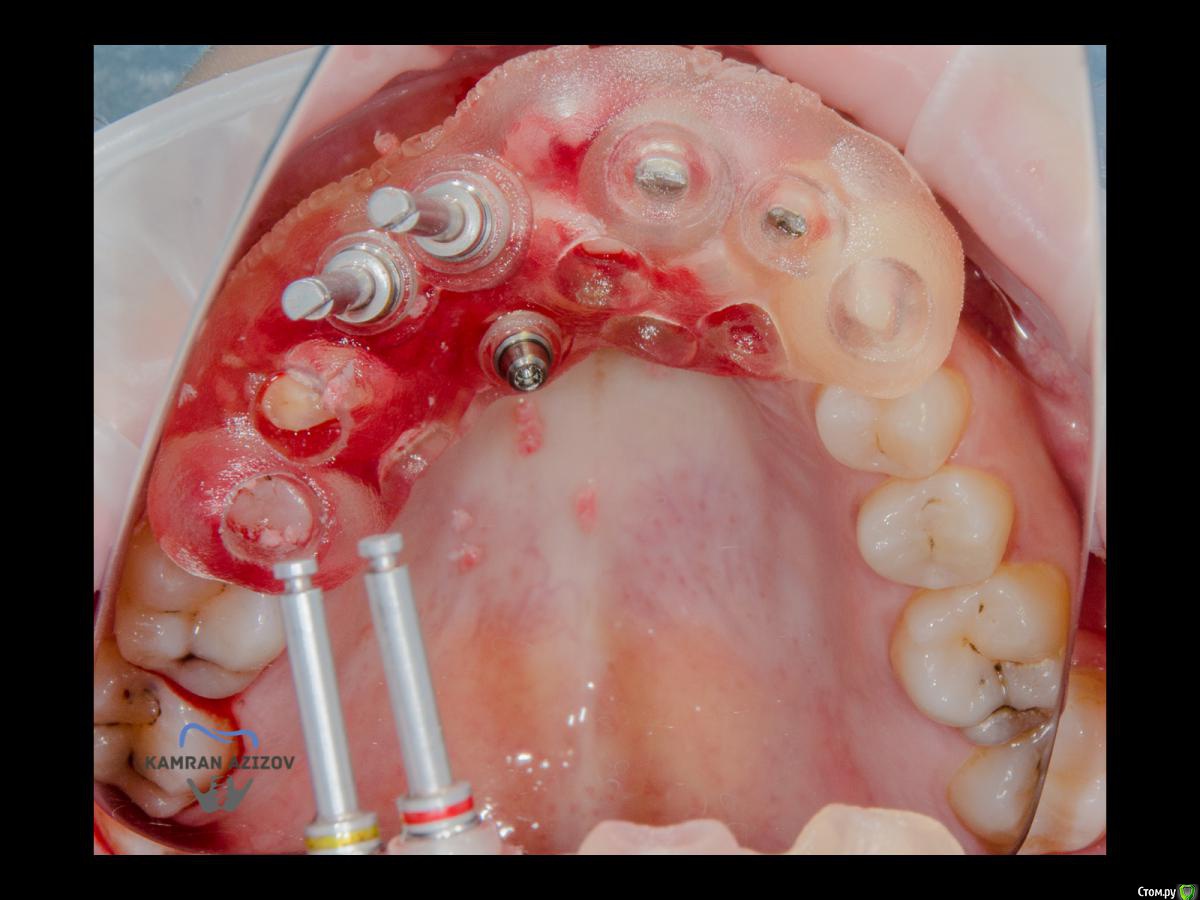

kamranchick Опубликовано 6 апреля, 2019 Поделиться Опубликовано 6 апреля, 2019 (изменено) Хай Гайсдавно ничего не комментировал и не выкладывал, что то настроения не было, да и муза не посещалаСитуация следующаяпришла пациентка, жалобы на неприятный запах из рта, сначала не понял что за хрень, ну как распилил мост понял че к чему... халтура.Ну и по кейсуУдаление клыка и 2ки, через 2 месяца навигация, имплантация + Шашлыки по карлоссу, смена формиков, временное протезирование. только мягкие ткани, Изменено 6 апреля, 2019 пользователем kamranchick 7 1 Ссылка на комментарий

jm3300 Опубликовано 6 апреля, 2019 Поделиться Опубликовано 6 апреля, 2019 А 12- на винтовой? Ссылка на комментарий

kamranchick Опубликовано 7 апреля, 2019 Автор Поделиться Опубликовано 7 апреля, 2019 Тут все на винтовой фиксации Ссылка на комментарий

Nazim_NV86 Опубликовано 7 апреля, 2019 Поделиться Опубликовано 7 апреля, 2019 Пятый Без пина шаблон не держался? Ссылка на комментарий

kamranchick Опубликовано 8 апреля, 2019 Автор Поделиться Опубликовано 8 апреля, 2019 Пятый Без пина шаблон не держался? держался) но сделали на всякий случай) Ссылка на комментарий